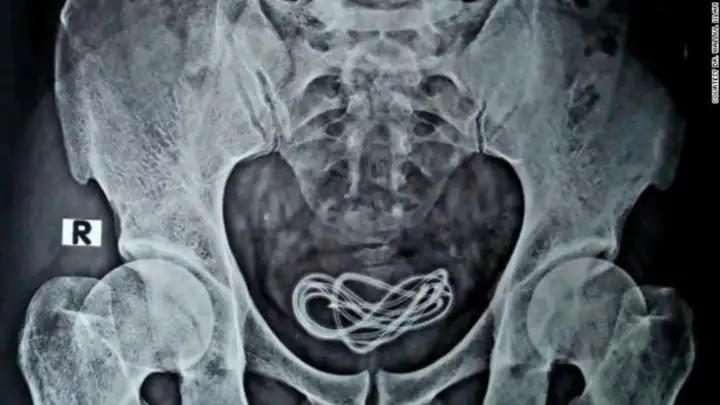

Fue en ese momento que una radiografía reveló que el hombre tenía un cable de cargador de 60 centímetros de largo dentro su vejiga, el cual fue insertado a través de su uretra, el tubo que va desde el pene a la vejiga.

“Luego hice una incisión allí y saqué el cable, que en realidad era un cable de cargador de más de 60 centímetros de largo”, dijo Islam.